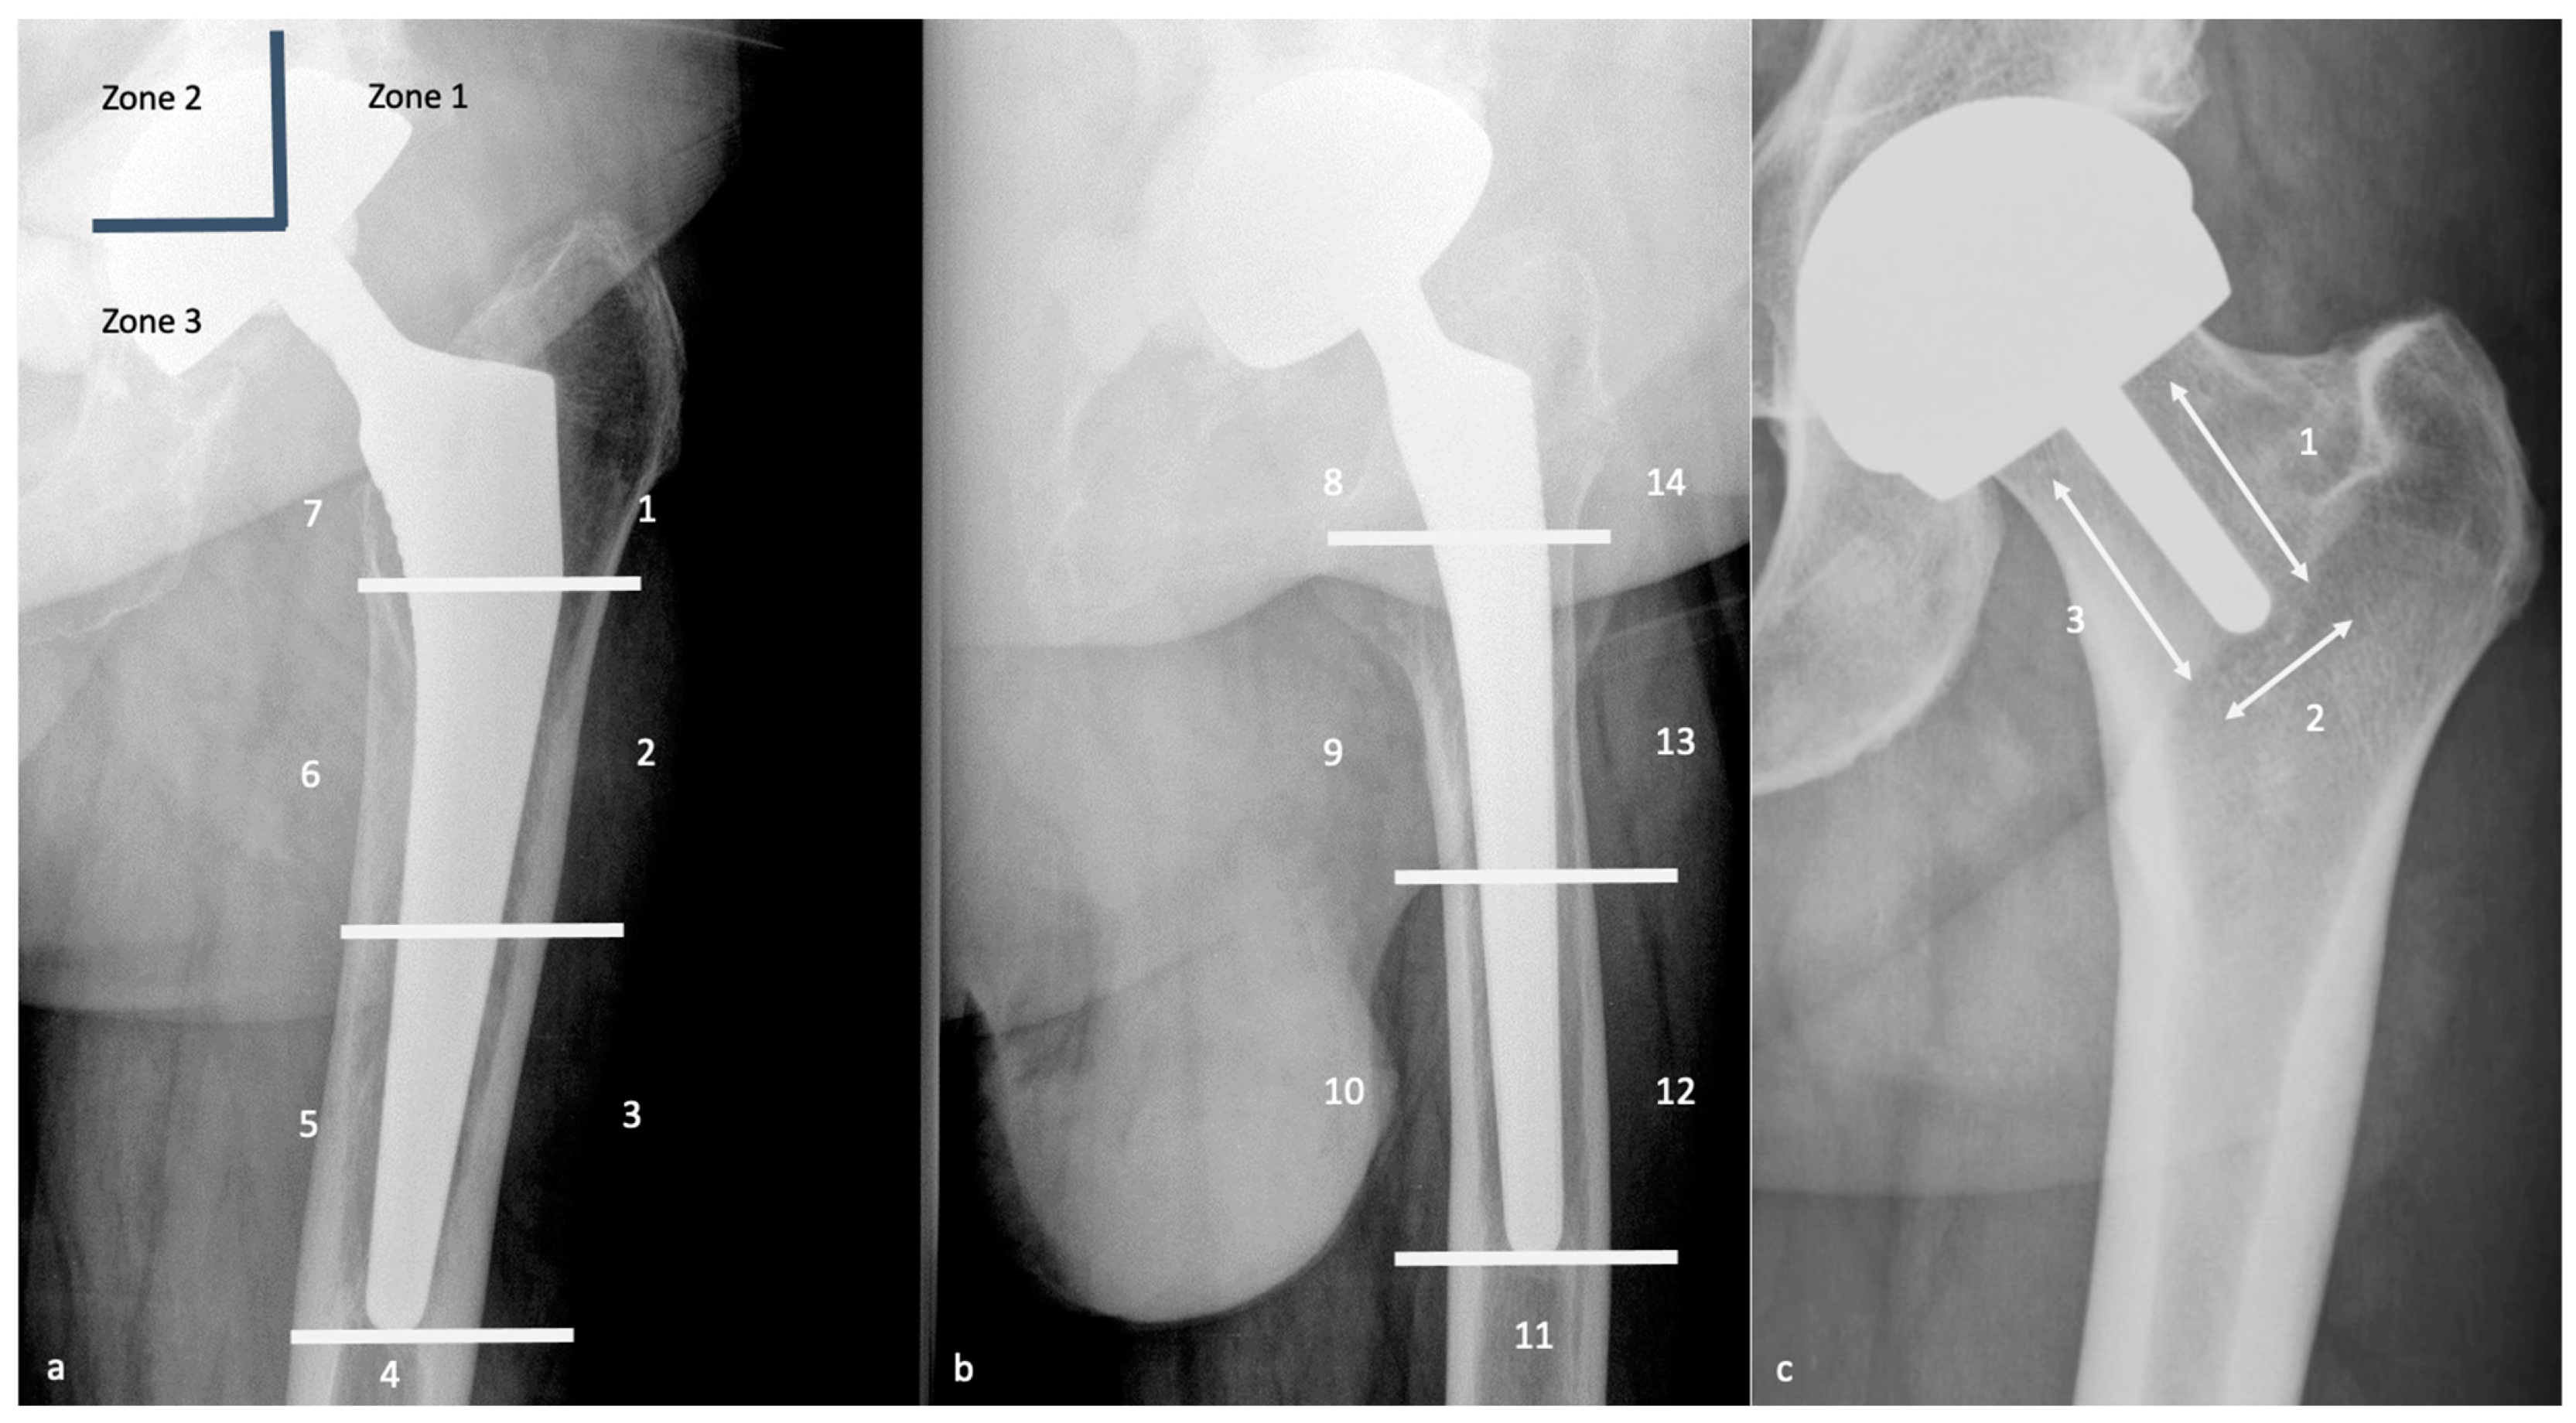

4.3.3. Radiographs, Tomosynthesis, and CT

- Engh, C.A.; Massin, P.; Suthers, K.E. Roentgenographic Assessment of the Biologic Fixation of Porous-Surfaced Femoral Components. Clin. Orthop. Relat. Res. 1990, 257, 107–128. [Google Scholar] [CrossRef]

- Roche, O.; Girard, J.; Canovas, F.; Migaud, H.; Bonnomet, F.; Goldschild, M.; Le Béguec, P. Assessment of Fixation in Cementless Femoral Revision of Total Hip Arthroplasty: Comparison of the Engh Score versus Radiolucent Line Measurement. Int. Orthop. 2016, 40, 907–912. [Google Scholar] [CrossRef] [PubMed]

- Canovas, F.; Putman, S.; Girard, J.; Roche, O.; Bonnomet, F.; Le Béguec, P. Global Radiological Score for Femoral Cementless Revision Stem. Int. Orthop. 2018, 42, 1007–1013. [Google Scholar] [CrossRef]